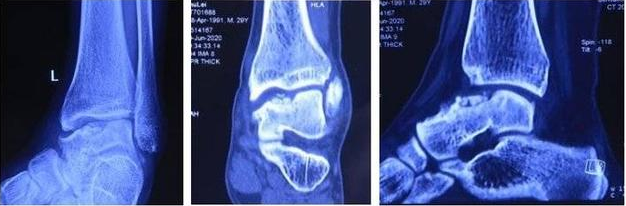

患者,男,28歲,左踝關節疼痛1年,加重3個月,影像學表現為左距骨內髁壞死、塌陷,面積約3*2cm大小。距骨壞死的治療,對直徑在2cm以內的距骨壞死,可以采用自體股骨髁骨軟骨移植、自體帶骨膜髂骨移植等方法,但對于直徑超過2cm的距骨壞死,尤其是年輕患者,一直是治療的難點。搜索國內外文獻,對于超過2cm距骨壞死,一般采用踝關節融合、踝關節置換、同種異體距骨移植、全距骨置換等方法。但上述方法均有弊端:采用關節融合,患者喪失踝關節功能;踝關節置換、全距骨置換對于年輕、距骨單髁壞死患者,創傷大,且需要多次的返修手術;國外有采用同種異體新鮮距骨移植的報道,但目前國內還沒有相關的骨組織工程庫。經手術團隊術前充分討論,認為3D打印技術因其個性化的設計已經越來越多地應用于臨床,決定對患者行3D打印距骨部分置換手術。

△術前3D打印設計